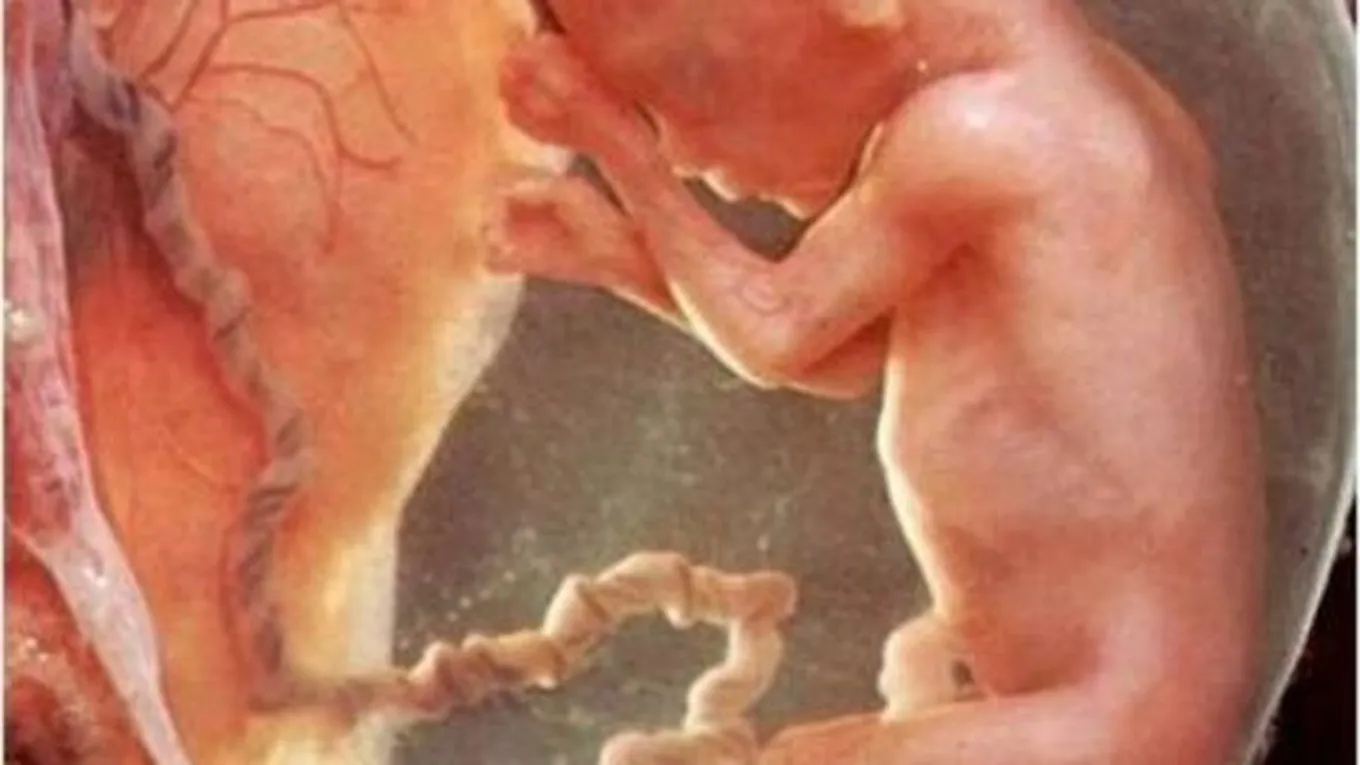

تقع المشيمة بداخل رحم الأم ويقتصر وجودها بداخل الرحم على وجود جنين ملتصق بجدار رحم الأم، حيث يحفّز الجنين الرحم على البدء بتكوين المشيمة، والتي تتشكّل من عدد كبير جداً من الشعيرات الدموية، وتجتمع مع بعضها لتتخذ هيئة دائرية مسطحة مرتبطة بجدار الرحم، وتعتبر المشيمة نقطة الربط الوحيدة بين الجنين عبر الحبل السري وبين الأم عبر الأوعية الدموية المرتبكة بالمشيمة والمغذية لها، وتبقى المشيمة بداخل الرحم طوال فترة الحمل إلى أن تتمّ عملية الولادة، حيث يتم سحب المشيمة خارج الرحم بعد خروج الجنين من الرحم.

تنشأ المشيمة من ارتباط أنسجة الجنين والأم ببعضها البعض، والتي تتّخذ شكل أعمدة المرتبطة مع بعضها البعض على شكل كيس يغلف الجنين من الخارج، حيث تخترق هذه الأعمدة البطانة الرحمية من أحد جهاتها كما تتفرع إلى زغابات صغيرة تحتوي كل من دم الجنين والأم دون أن تخلط بينهما، حيث يعبر كل من الغذاء والأوكسجين من دم الأم إلى دم الجنين عبر الأغشية الموجودة في هذه الزغابات، أمّا طول المشيمة لدى الأم الحامل في آخر مراحل حملها فيصل إلى 9 بوصة كما يصل وزنها إلى 500 غم، وتكون المشيمة أكثر سمكاً من الوسط عن الأطراف حيث يصل أقصى سمك لها إلى 1 بوصة.